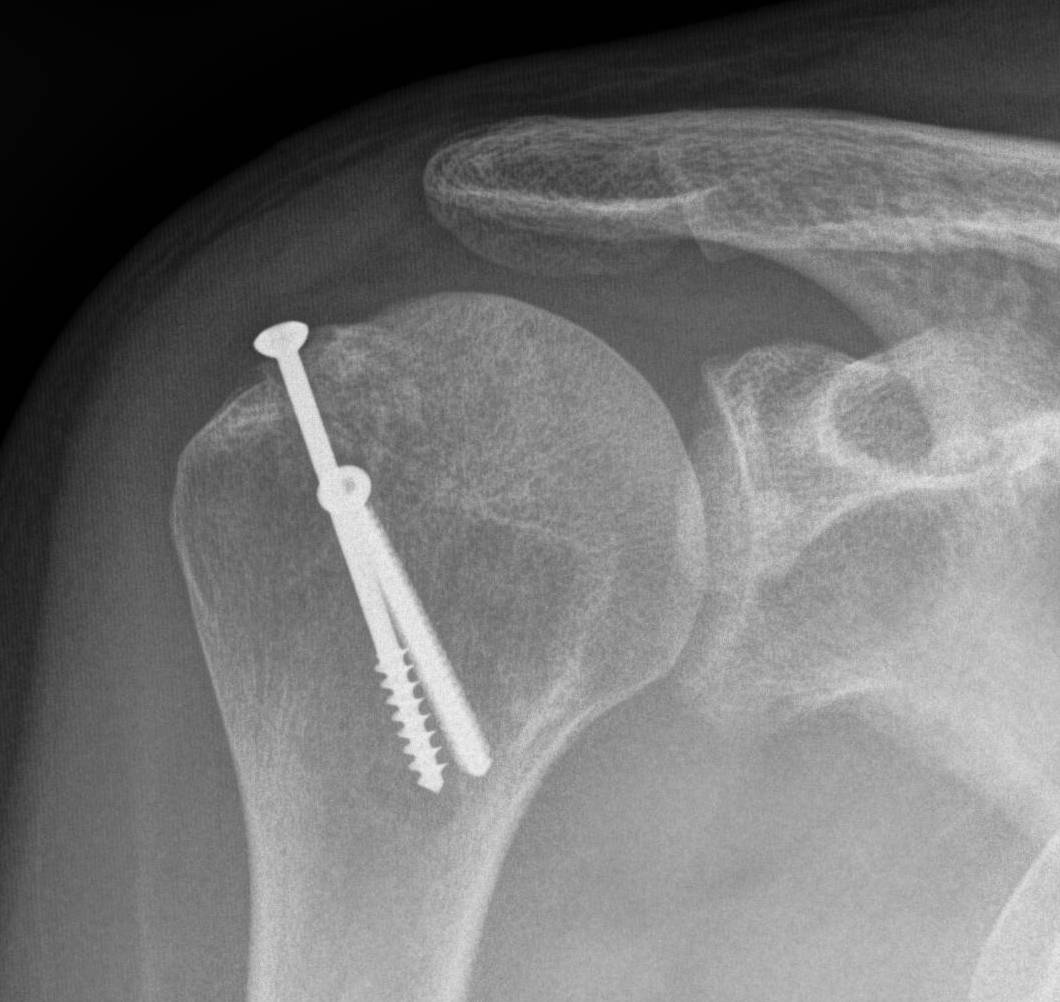

Distal tibial allograft (DTA)

- systematic review of DTA for shoulder instability with bone loss

- 8 studies and 329 patients

- recurrent instability 1.5%

- complication rate 7%

- hardware complications 4%

- graft resorption 37%